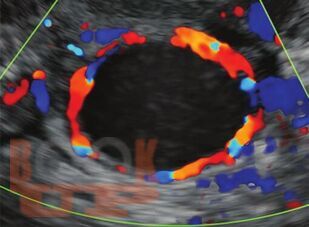

The book discusses in detail the use of Doppler for the differential diagnosis of different endometrial and myometrial lesions, ovarian and tubal lesions. The important role of Doppler for deciding stimulation protocols for patients on assisted reproductive technology treatment, for assessment of functional maturity of follicles and endometrium and also correlation of these Doppler changes with hormonal level fluctuations has also been described. This is truly a to the point, easy-to-read and reference book for the role of Doppler in Obstetrics and Gynecology and Infertile patients. Proved to be of great help to the cliniciansgynecologists and radiologists as a practical guide and a quick reference for the use of Doppler technology for better diagnosis with ultrasound.